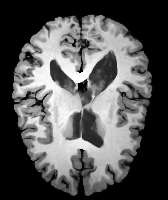

Image Manual Seg DA-1 Mono-21 DA-21 Mono-65 Refer to caption Refer to caption Refer to caption Refer to caption Refer to caption Refer to caption

Figure 2:  Examples of knee MRI registration (top) and brain MRI segmentation (bottom) results. Top: The first two columns are the moving image/segmentation and the target image/segmentation followed by the warped moving images (with deformation grids)/segmentations by different models. Bottom left to right: original image, manual segmentation, and predictions of various models. Mono-i𝑖i and DA-i𝑖i represent the mono- and DA models with i𝑖i manual segmentations respectively.

Results: All trained networks are evaluated using Dice overlap scores between predictions and the manual segmentations for the segmentation network, or between the warped moving segmentations and the target segmentations for the registration network. Tabs. 1 and 2 show results for the knee and brain MRI experiments respectively in Dice scores (%). Fig. 2 shows examples of knee MRI registrations and brain MRI segmentations.

Brain results: Dice scores for segmentation and registration increase by about 2.6 and 3.5 respectively for the cortical structures of the brain MRIs.

Qualitative results: DA achieves more anatomically consistent registrations than the mono-networks on the knee (Fig. 2) and Brain MRI samples (see supplementary material).

Image Manual Seg DA-1 Mono-5 DA-5 Mono-200 Refer to caption Refer to caption Refer to caption Refer to caption Refer to caption Refer to caption

Figure 4: Examples of brain MRI registration (top) and knee MRI segmentation (bottom) results. Top: The first two columns are the moving image/segmentation and the target image/segmentation followed by the warped moving images/segmentations by different models. Bottom left to right: original image, manual segmentation, and predictions of various models. Mono-i𝑖i and DA-i𝑖i represent the mono- and DA models trained with i𝑖i manual segmentations respectively.